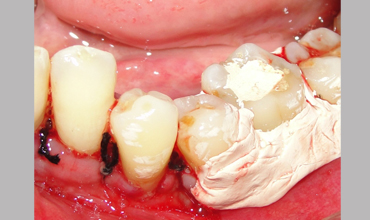

NON SURGICAL MANAGEMENT OF ENDODONTIC LESION AND SURGICAL MANAGEMENT OF PERIODONTIC LESION